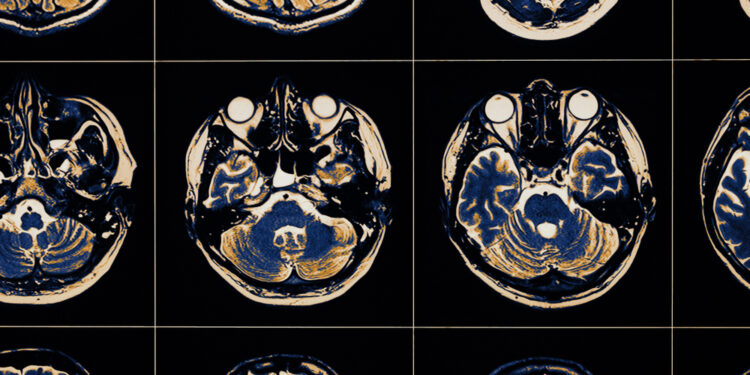

Diagnozuojant šią būklę reikalingas tiek išsamus fizinis bei neurologinis ištyrimas, tiek specifiniai tyrimai. Ligoninėje dažniausiai taikomi šie diagnostiniai metodai:

- Kompiuterinė tomografija (KT);

- Magnetinio rezonanso tomografija (MRT);